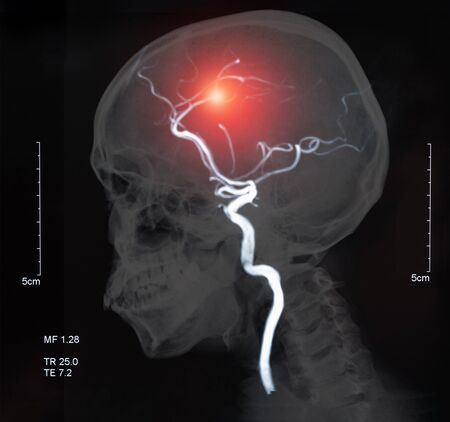

뇌졸중 징후이 발생하면 MRI로 진단해 뇌졸중 예방과 선제적 치료를 하더라고요. 뇌졸중 진단을 받으면 증상의 정도와 환자의 정황에 따라 약물치료와 수술이 이뤄진다고 하더라고요. 근래에는 시술이 발달해 골든타임 내에 병원에 오면 막힌 혈관에 스텐트라는 그물을 투여해 혈전을 삭제하는 뇌혈관 중재를 통해 후유증을 감소시키며 실리적으로 치료할 수 있고요.

1. 약물치료뇌경색은 혈전을 약물로 녹여 다스려 낫게하는 혈전용해 법으로 치료가 가능해 뇌졸중 발생 후 3시간 이내에 병원에 착근해야 해요. 혈전용해 치료는 합병증과 재발 방지를 위해 치료하며, 뇌출혈 시 수술적 치료가 소요된다고 하더라고요.2. 외과적 치료뇌지주막하 지나친 두통과 구토를 대동하기에 뇌혈관조영술로 출혈 부위를 찾아서 수술하면 됩니다 해요.3. 뇌졸중 예방 치료뇌경색은 혈정 예방제로 다스려 낫게하는데 동맥경화로 뇌혈관이 좁아지고 막혔을 때 수술이나 혈관 확장을 통해 치료가 가능하다고 하고요.